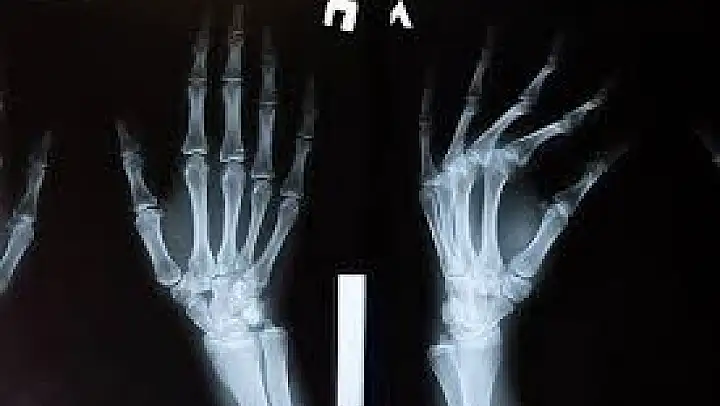

Parmak çıtlatmak için hangi yöntem kullanılırsa kullanılsın, çıtlatma sesi aynı şekilde çıkar. Eklemler arasındaki boşluk artınca, eklem sıvısı içindeki gazlar minik baloncuklar oluşturur; artan boşluğa dolan ekstra sıvı bunların birleşip daha büyük baloncuk oluşturarak patlamasına neden olur.

Yıllar boyunca parmak eklemlerini çıtlatmanın eklem etrafındaki kıkırdağa zarar vereceği yaygın bir kanı olmakla birlikte, aslında bu konuda fazla delil bulunmuyor.

O halde parmak çıtlatma ile eklem hastalıkları bağlantısı nasıl kuruluyor? Artrit hastalığı olanların eklemlerindeki kıkırdak hasarlı olduğu için arada bir parmakları kendiliğinden çıtlar. Ama bu hasarın nedeni değil, sonucudur. Artritin nedenleri arasında yaşlılık, genetik faktör, elin incinmesi, ömür boyu elle ağır iş yapılması gibi etkenler sıralanıyor.